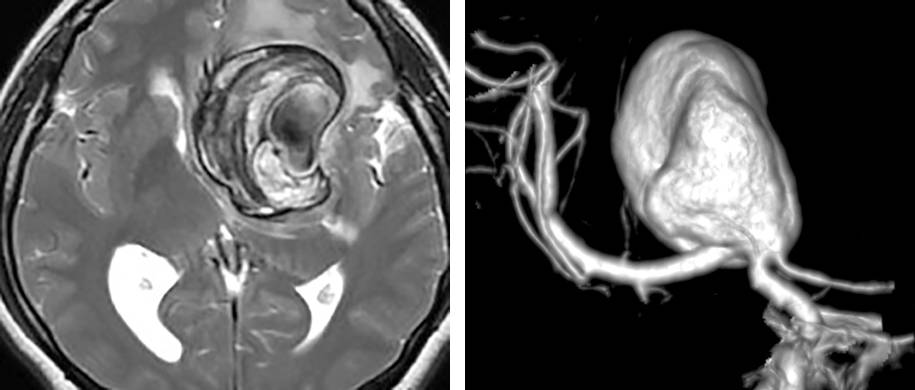

图1. 左侧颈内动脉分叉部动脉瘤,大小6cm,伴钙化和部分血栓形成,传统的显微手术夹闭不可行。治疗方案为:颅外段ICA-M2的高流量搭桥、结扎脉络前动脉以远的ICA(Hunter方式)、阻断同侧A1逆流进入瘤腔的血流。后文有展示本例术中情况的图片。

图11. 图1所示患者的术后血管造影证实动脉瘤已被孤立不显影,同时桥血管血流通畅。